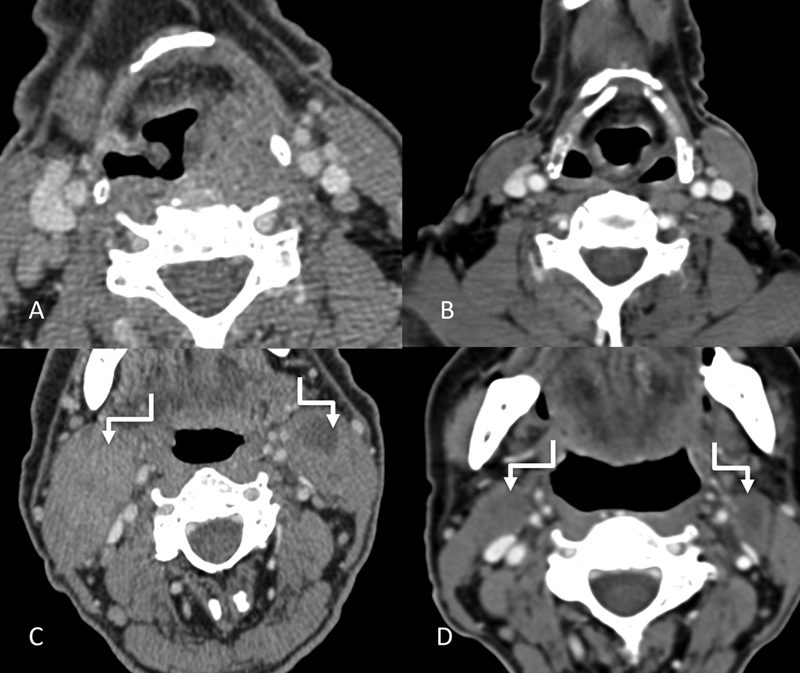

| Figure 13:Imaging of post cricoid cancer. Axial and sagittal CT images (A–C) showing a mass (straight arrows) involving the post cricoid region and a metastatic right level II node (shouldered arrow).